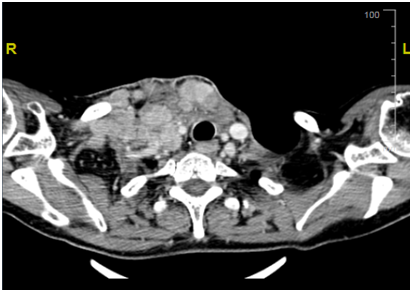

Figure 1 a) Response after Lenvatinib.

b) Disease prior to Treatment with Lenvatinib.

Our patient is a 55yrs. old female with long standing history of Goitre. She underwent total thyroidectomy after confirming Papillary Thyroid cancer on FNA at presentation with slowly progressing neck mass over a course of 1yr. Initial TNM stage showed a T3 N1 M0 Papillary thyroid tumour with extra capsular extension. She proceeded to have radio iodine ablation in May 2016 with 5000Mbq which showed uptake in thyroid bed and Rt neck nodes at level 2. She was then maintained on TSH suppressive dose of thyroxine. Unfortunately, she suffered a relapse in the neck with neck nodes 3 months later i.e. in august 2016 and proceeded to have neck clearance. Again nodes in the RT neck were noted along with extra capsular extension. Pathology, however, showed anaplastic thyroid cancer. Within 6 weeks from her second surgery she came back with rapidly progressing bilateral lower neck nodes. She had a CT which confirmed the recurrence with no distal metastasis. Her recurrence, now second after initial surgery, was deemed inoperable due to the tumour being wrapped around the carotid artery. She proceeded with External Beam Radiotherapy for local control. She progressed on radiotherapy within 2weeks of the start of treatment. This was confirmed on repeat CT scan. No distal metastasis was detectable. Unsurprisingly patient’s thyroglobulin levels were never very high (max level of 20.6). Subsequent levels were within normal limits with no detectable Anti Thyroglobulin Antibody. At this point patient was started on 24mg of Lenvatinib. On her next follow up after 2weeks patient had a complete clinical resolution of her neck nodes and a subcutaneous suprasternal mass as seen previously showed considerable shrinkage. Patient remained troubled with grade 2 fatigue and anorexia but nothing else. At her next appointmentafter2 weeks she had complete disappearance of her disease so much so that a crater was left in suprasternal area i.e. site of her previous subcutaneous tumour extension. Due to persistent fatigue and anorexia dose of Lenvatinib was reduced to 14mg which she is tolerating well. She had a CT at 6weeks which confirmed complete resolution of her disease and no metastasis. She has recently undergone debridement of the lower anterior neck wound and no disease has been detected on biopsy. She awaits her next staging CT in near future (Figure 1).